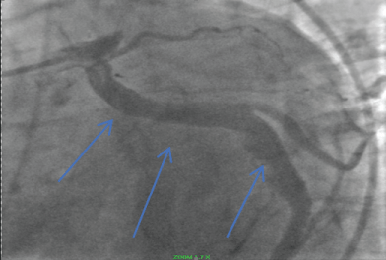

Thrombus was identified in the LAD (Figure 11).

Figure 11: LAD clot (blue arrow) 2018. View Figure 11

The patient was treated for 72 hours with aspirin and ticagrelor. The hope was to dissolve the thrombus and determine the degree of underlying atherosclerosis.

Follow up angiography revealed that the thrombus burden in the circumflex and LAD was unchanged. The patient had no further clinical symptoms. Aspirin was continued and heparin was initiated. Additionally, the patient was started on warfarin therapy after discussing the risks and benefits. Once the INR was 2.5 the patient was discharged to follow up.